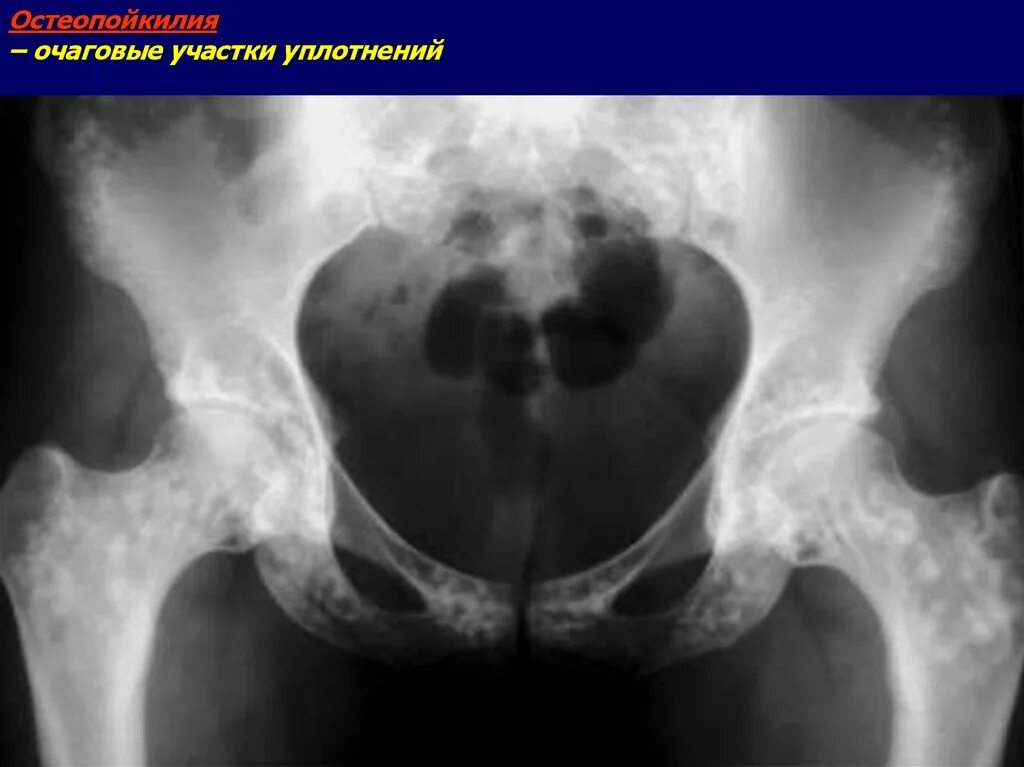

Склероз вертлужной впадины